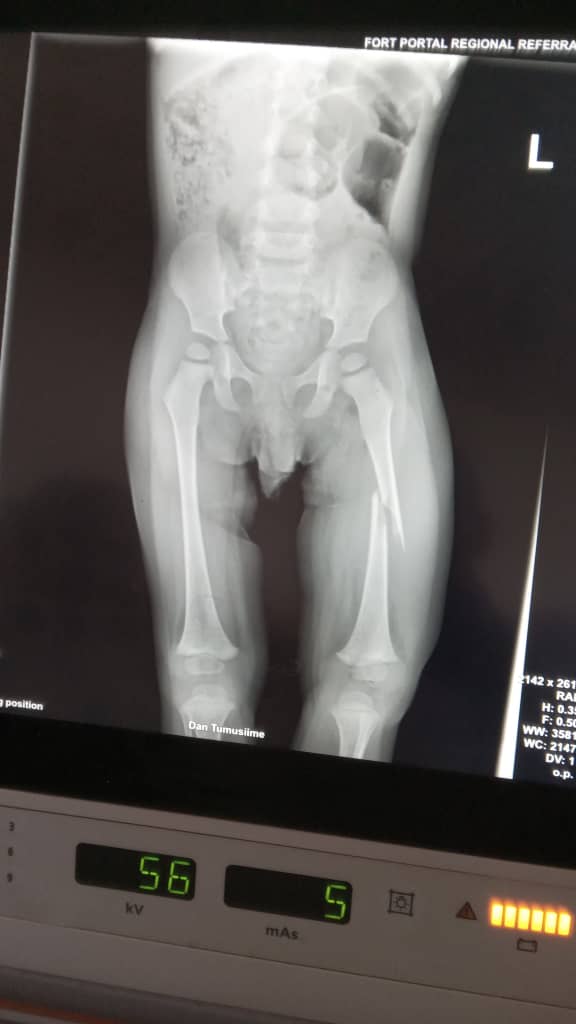

Am Montag, den 14. Juli 2025, musste unser 1,5-jähriger Dan im Regionalkrankenhaus Buhinga medizinisch versorgt werden. Vermutlich durch einen Sturz hatte er sich den Oberschenkel gebrochen.

Nach einer sorgfältigen Untersuchung konnte der Bruch gerichtet und mit einem Gips stabilisiert werden. Dank der großzügigen Unterstützung durch unsere Freundinnen und Freunde vom Partnerschaft Gesunde Welt – Klinikverbund Südwest e.V. war es möglich, die Behandlungskosten sofort zu übernehmen. So konnte Dan schnell geholfen werden – nun hat er die besten Voraussetzungen, um bald wieder gesund und fröhlich durch den Garten zu tapsen.